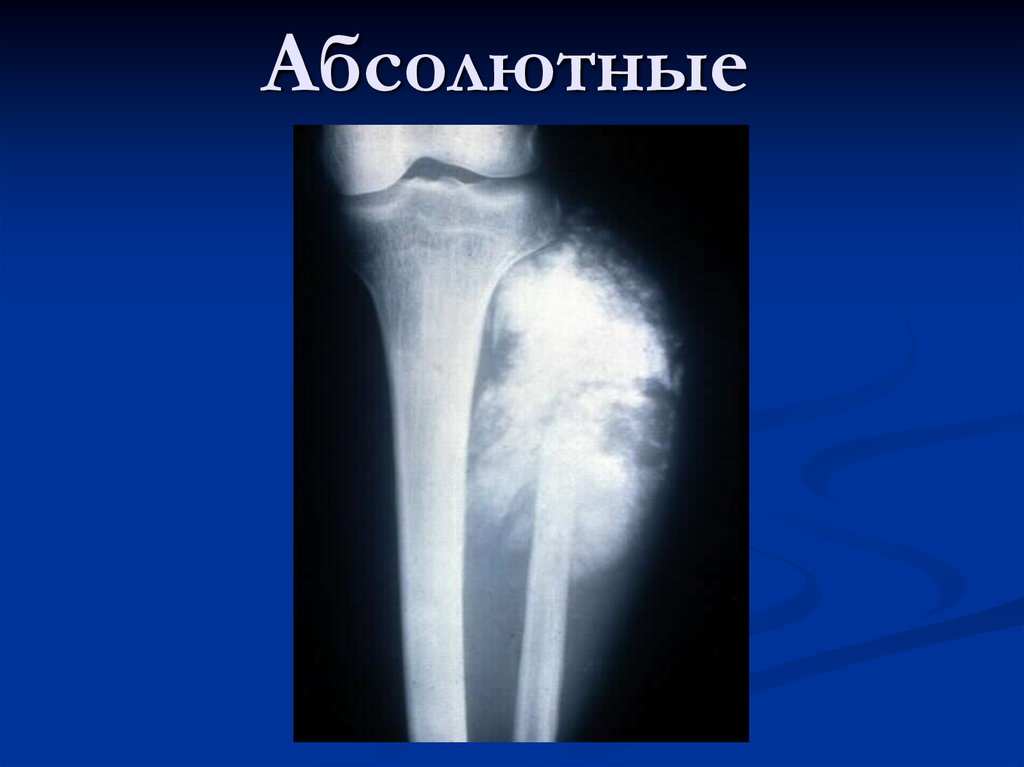

Остеосаркома коленного сустава: информация и поддержка